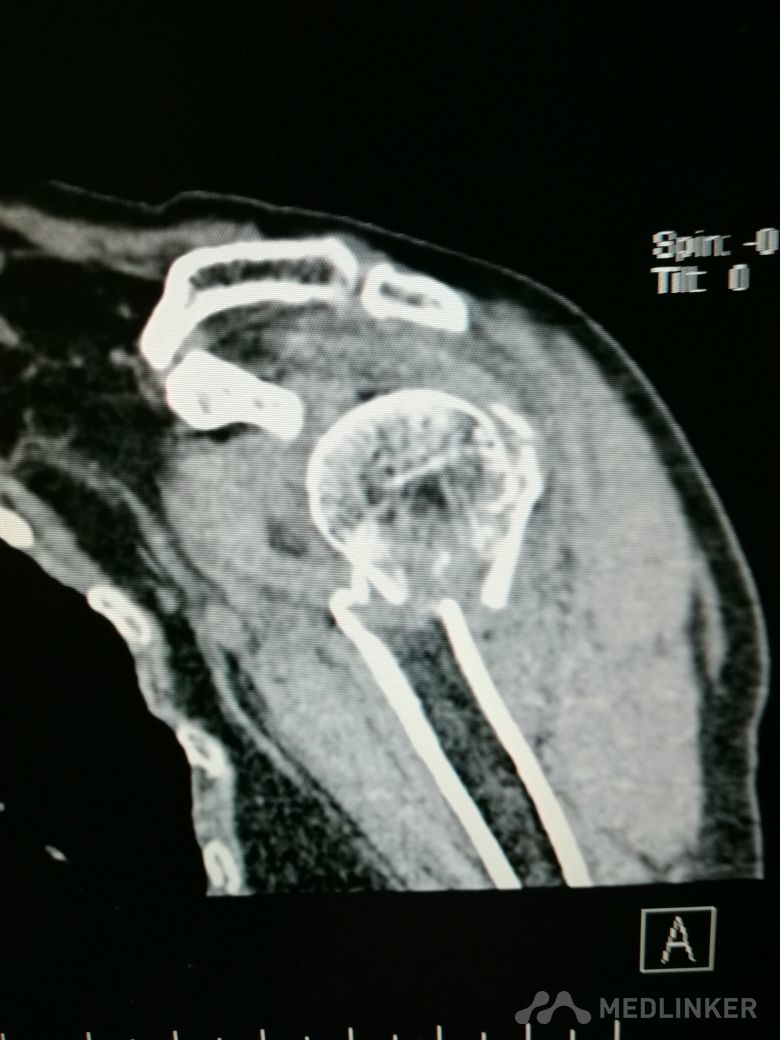

肱骨近端骨折 Neer IV型

患者,女性,55岁,因外伤致左肩疼痛六小时入院,既往无其他慢性病史

查体 右肩肿胀,畸形,活动受限,压痛,皮下淤血,右桡动脉搏动存在

完善相关检查,在腰麻下行右肱骨近端骨折切开复位内固定术

肱骨近端骨折占到肱骨骨折的45%,肱骨近端锁定钢板具有低切迹、高弹性、生物力学性能优良等特点,可以起到角度稳定控制旋转的作用。但是对于严重粉碎性肱骨近端骨折而言,单纯的肱骨近端锁定钢板不一定能够提供稳定的固定,手术之后仍有可能出现内翻塌陷、前后成角、螺钉切出、骨折畸形愈合、骨折不愈合等并发症。